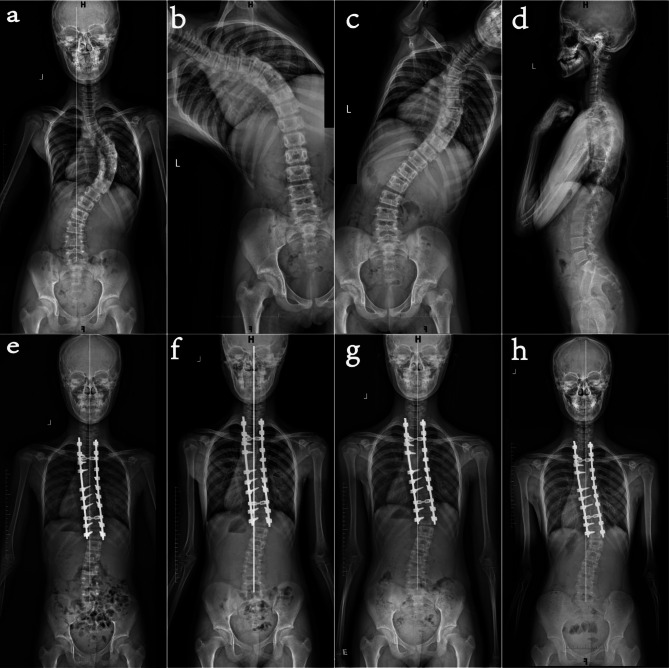

探讨Lenke 1型和2型青少年特发性脊柱侧凸(AIS)患者后路选择性胸椎融合术后远端附加现象进展的相关危险因素。对2015年12月至2021年12月期间接受后路选择性胸椎融合术的152例患者进行回顾性分析。其中48例患者术后出现远端附着现象。根据这种现象在随访中是否进展分为进展组和非进展组。单因素分析比较了两组之间的临床和影像学资料,而多因素logistic回归确定了独立的危险因素。48例术后远端接物患者中,37例(77.1%)为非进展性,11例(22.9%)为进展性。单因素分析显示,进展组和非进展组在Risser体征分级上存在显著差异(2.27±1.10∶3.73±0.87,P

To investigate risk factors associated with the progression of the distal adding-on phenomenon after posterior selective thoracic fusion in patients with Lenke type 1 and 2 adolescent idiopathic scoliosis (AIS). A retrospective analysis was conducted on 152 patients who underwent posterior selective thoracic fusion from December 2015 to December 2021. Among them, 48 patients experienced the distal adding-on phenomenon postoperatively. Based on whether this phenomenon progressed during follow-up, they were divided into progressive and non-progressive groups. Univariate analysis compared clinical and imaging data between the two groups, while multivariate logistic regression identified independent risk factors. Of the 48 patients with postoperative distal adding-on, 37 (77.1%) were non-progressive and 11 (22.9%) were progressive. Univariate analysis showed significant differences between the progressive and non-progressive groups in Risser sign grade (2.27 ± 1.10 vs. 3.73 ± 0.87, P < 0.001), number of segments between lowest instrumented vertebra (LIV) and the last substantially touched vertebra (LSTV) (-1.27 ± 0.79 vs. 0.51 ± 1.17, P < 0.001), preoperative clavicle angle (-2.55 ± 2.84 vs. -0.11 ± 2.82, P = 0.015), and preoperative trunk shift (21.05 ± 15.27 vs. 10.46 ± 13.32, P = 0.030). Multivariate analysis confirmed that lower Risser sign grade (OR = 0.16, 95% CI 0.03-0.82, P = 0.028) and fewer segments between LIV and LSTV (OR = 0.07, 95% CI 0.01-0.58, P = 0.013) were independent risk factors for the progression of the distal adding-on phenomenon. Lower skeletal maturity (Risser sign grade) and LIV located cephalad to LSTV are independent risk factors for the progression of the distal adding-on phenomenon in patients with Lenke type 1 and 2 AIS. For skeletally immature patients (Risser ≤ 3), LSTV should be preferentially chosen as LIV during surgery.